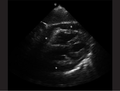

Abnormal